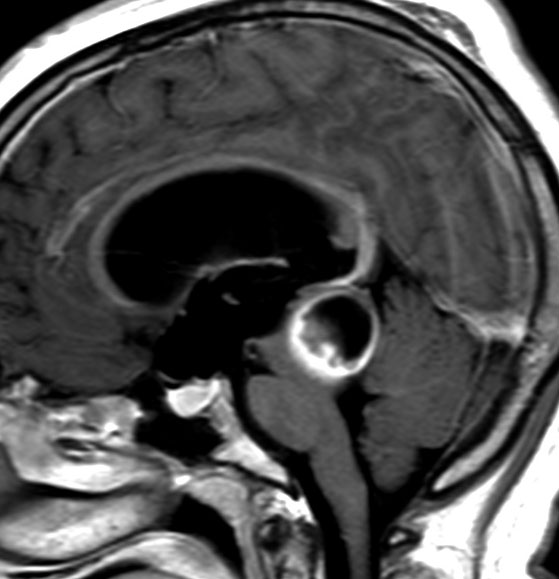

毛様細胞性星細胞腫であり,基本的には初回手術で全摘出できるのですが,現実的には,技術的に難しすぎるので部分摘出で終えることが多いでしょう。この子は,15歳の時に閉塞性水頭症のために,頭痛,嘔吐,意識障害,瞳孔不同となりました。開頭部分摘出術と第3脳室開窓術で回復して,その後にカルボプラチンとビンクリスチンの化学療法を受けました。

でも腫瘍増大が止められずに,発症1年後に54グレイ30分割の放射線治療を受けています。さらにその半年後くらいから再増大しましたが,スードプログレッションと考えられました。上左MRIは放射線治療前,上右MRIは放射線治療1年後です。毛様細胞性星細胞腫は放射線治療後に一過性増大(多くはのう胞性増大)することが多いです。

のう胞性拡大が止まらず,発症3年後にまた再開頭手術 (left occipital transtentorial approach) で亜全摘出しました。右は術後の画像です。初発時の最初の手術で亜全摘出あるいは全摘出 gross total removalできていればと思える例です。